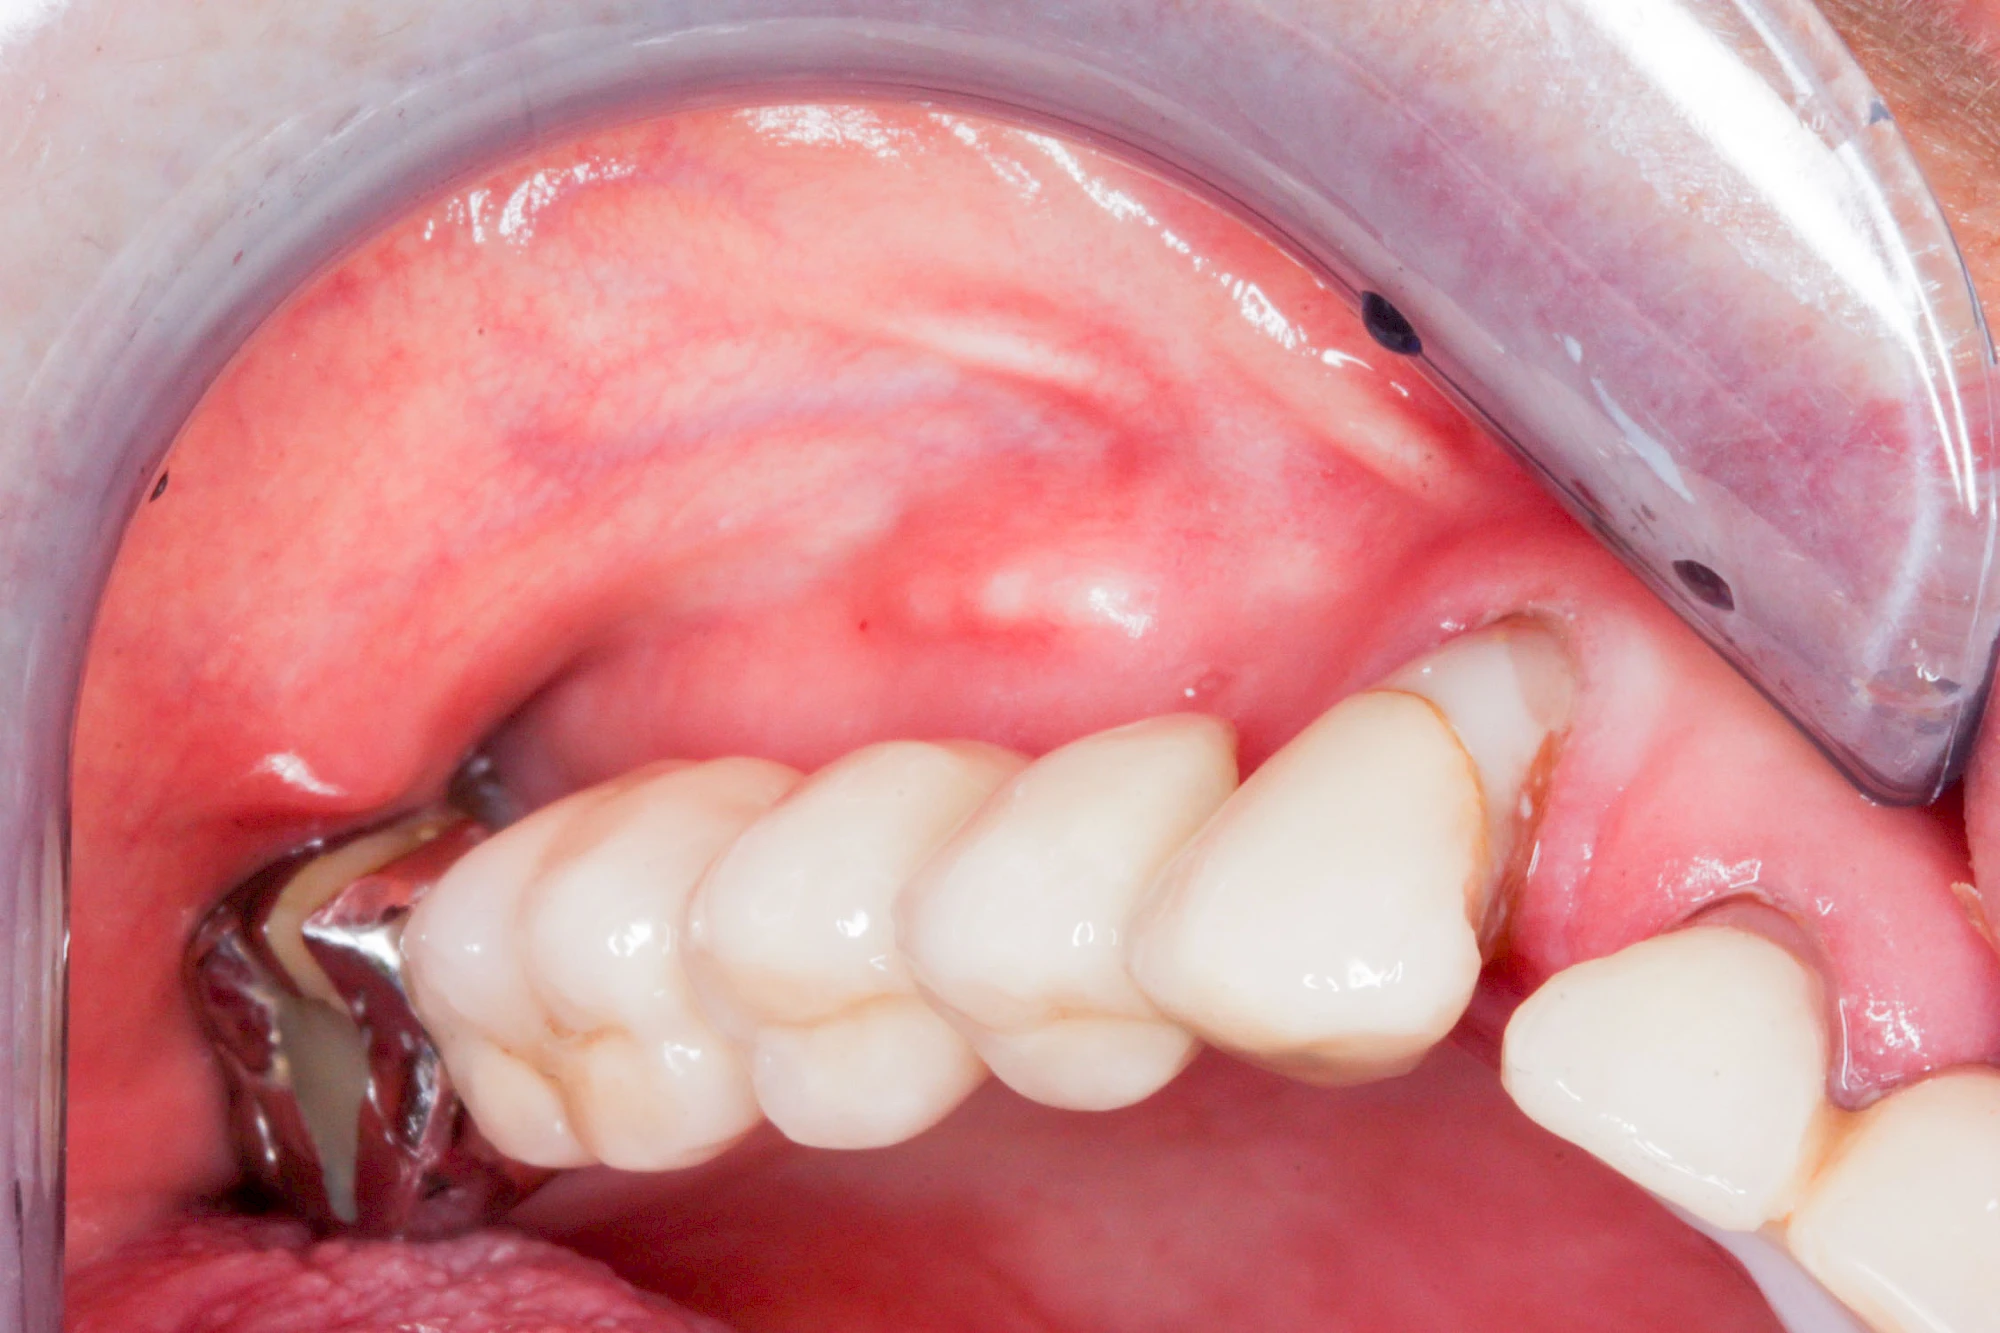

Überbeine im Bereich der Kiefer sind gar nicht so selten. Häufiger im Bereich der Seitenzähne unterhalb des Zahnfleisches, aber auch in der Mitte vom Gaumen. Überbeine haben in dem Sinne keinen Krankheitswert, müssen also nicht operativ entfernt werden, wenn diese nicht stören. Überbeine können ein Anzeichen für Knirschen und Pressen sein.